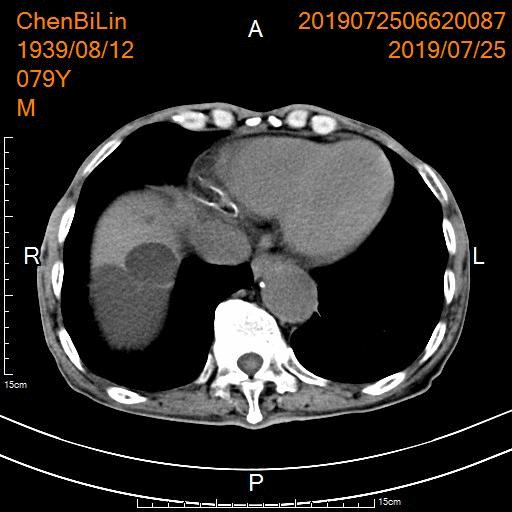

老年男性,腹部闷胀痛1年余。CT检查显示肝脏多发、巨大囊肿,最大者直径达20cm。患者行CT引导下肝穿刺置管引流及硬化治疗后,腹胀痛症状即刻缓解。

CT显示肝脏多发、巨大囊肿